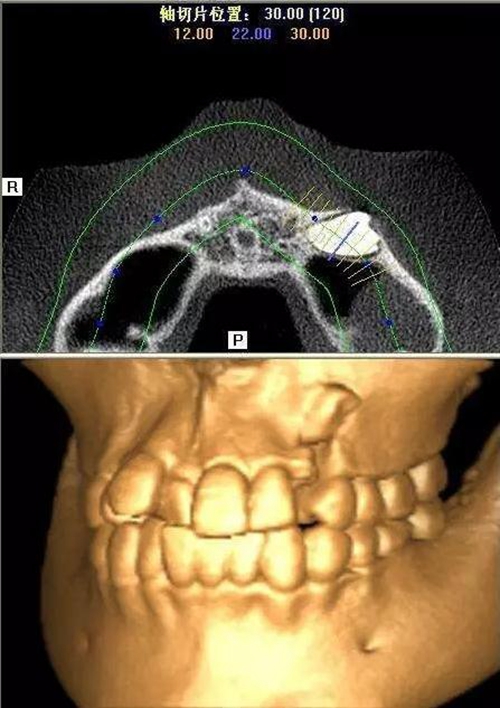

本案:患兒,女,14歲,因牙齒矯正來院,檢查見83滯留,43未見萌出,拍片發(fā)現(xiàn):43埋伏阻生于31、41、42根尖下方,按照正畸診療計劃,擬行43拔除術(shù)。

CBCT顯示

設(shè)計冠切的位置

橫斷牙冠,注意深度的把控

為了減少骨創(chuàng),“T”型分割牙冠